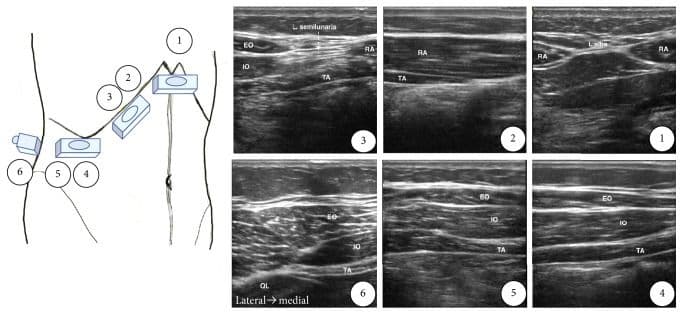

Середньоаксилярний ТАР-блок

Для виконання цієї блокади лінійний датчик розміщують в аксіальній площині по середній пахвовій лінії між краєм реберної дуги та гребенем клубової кістки. Візуалізують три шари м'язів стінки: зовнішній та внутрішній косі м'язи живота, а також поперечний м'яз живота. Ціллю є фасціальна площина між внутрішнім косим м'язом живота та поперечним м'язом живота. Голку вводять по передній пахвовій лінії, і кінчик голки просувають до досягнення фасціальної площини між внутрішнім косим м'язом живота та поперечним м'язом живота приблизно по середній пахвовій лінії [5,6,13,25].